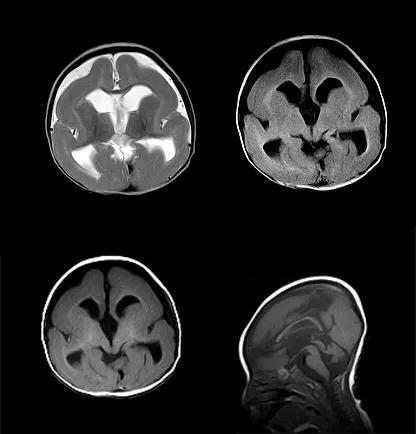

Dandy-Walker 综合征

Dandy-Walker 综合征(Dandy-Walker Syndrone DWS)又叫第四脑室孔闭塞综合征,是一种后颅窝先天发育畸形,是一种较罕见的颅脑先天发育异常

DWS 可见于各个年龄段患者,部分病人可无症状

MRI 是诊断 DWS 的最佳影像学手段

典型表现包括:小脑发育异常或蚓部缺失,小脑半球分离;‚第四脑室扩大并与后颅窝贯通,伴有横窦、窦汇及小脑幕上移;ƒ幕上脑室对称性扩张

常合并颅内其它畸形

case 1:男性,11 个月 10 天。突发呼吸急促、*吟呻** 8 小时

诊断:Dandy-Walker 综合征。

case 2:女性 ,37 岁。步行不稳 3 个月。

诊断:Dandy-Walker 综合征合并脂肪瘤。